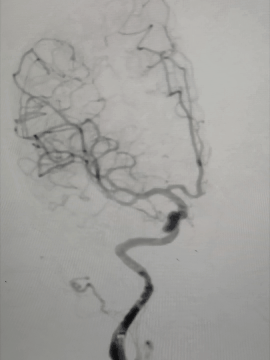

术后造影

术后正位即刻造影显示:Surpass Streamline血流导向密网支架整体贴壁良好,瘤腔内造影剂明显滞留。